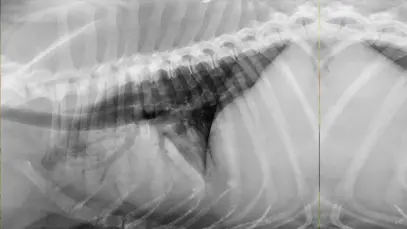

Tal como os humanos a gestação de cachorro também é um período sensível para a cadela prenhe e demanda cuidados especiais do tutor. A fêmea precisa de ajuda para ter […]